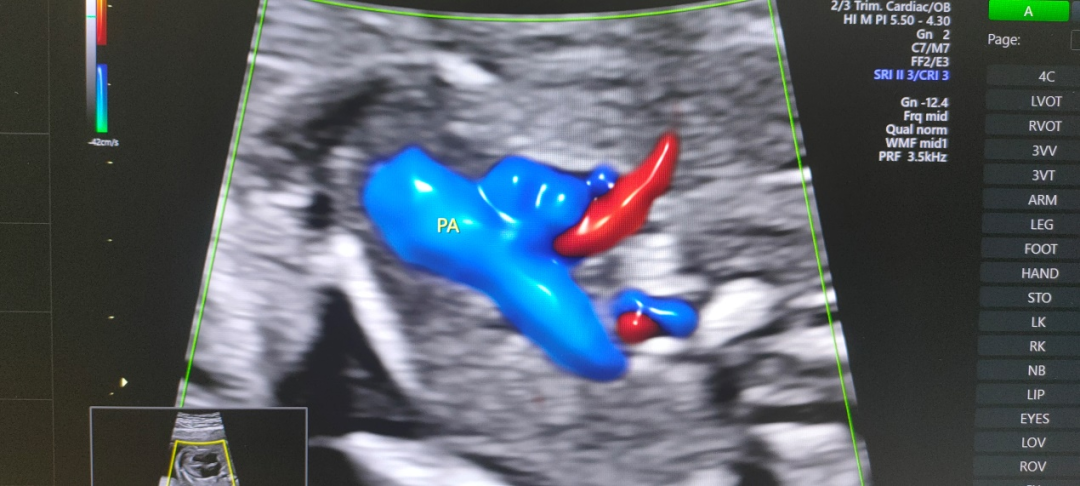

金标版GE-E10四维彩超是美国GE公司四维彩超的最新成员,专为尖端的妇女健康影像而设计,可广泛应用于妇产超声临床领域。尤其在产前超声筛查、孕早期成像、胎儿心脏成像、妇科泌尿和生殖医学等领域表现出色。

360°立体动态成像技术可清楚地显示子宫情况、输卵管形态、输卵管积水、通畅情况、伞端是否与周围组织粘连,大大提高输卵管的显示率和准确性;还能全方位立体动态地观察到胎儿生长发育状况。